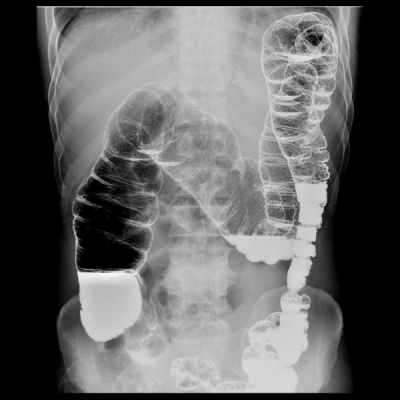

Рентген органов пищеварительной системы (пищевод, желудок, толстая кишка)

Показания к рентгенологическому исследованию органов пищеварительной системы:

- Подготовка к плановой операции

- Выявление органических заболеваний (опухолей) пищевода, желудка,12 пк, толстой кишки, оценка объема поражения.

- Выявление инородных тела пищевода, желудка, тонкого и толстого кишечника.

- Непроходимость тонкого и толстого кишечника.

- Динамическое наблюдение за состоянием отделов пищеварительного канала в процессе лечения и (при необходимости) в разные сроки после завершения лечения.

- Оценка отделов толстой кишки после операций и выведения стомы (перед операцией по восстановлению толстой кишки).

Методики исследований органов пищеварительной системы:

Рентгеноскопия и рентгенография органов брюшной полости выполняется в 2х проекциях – прямой и боковой, в вертикальном и/или горизонтальном положении. Специальной подготовки не требуется.